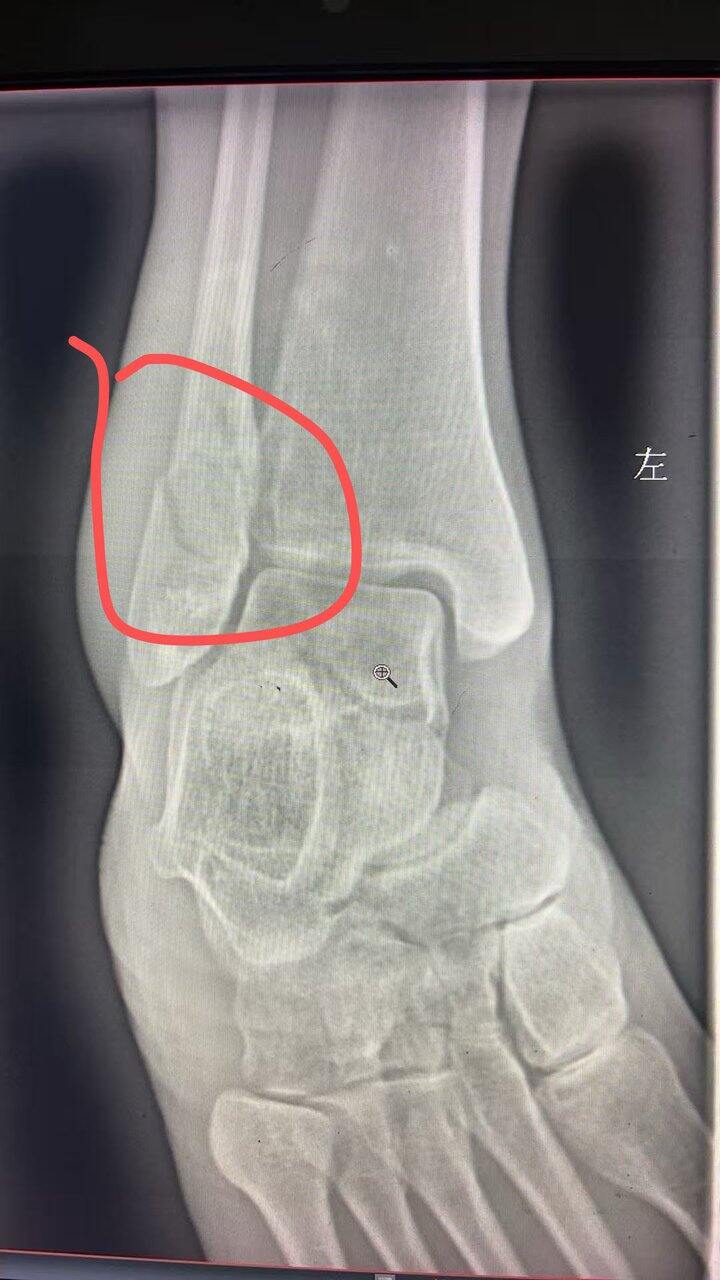

大冤种骨折,今天第一天

看看我啥时候恢复[皱眉][皱眉]